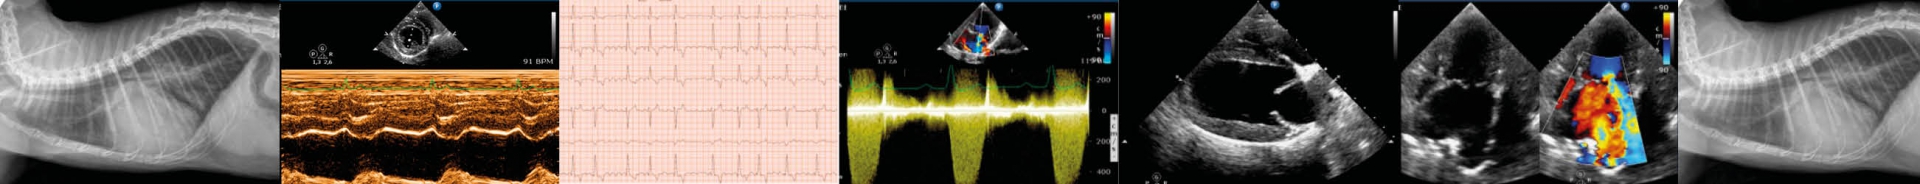

In order to detect any change in the heart's electrical/mechanical activity and identify potential treatment, patients may undergo standard ECG, chest X-ray, ecocardiography (2D, M-mode, Doppler).